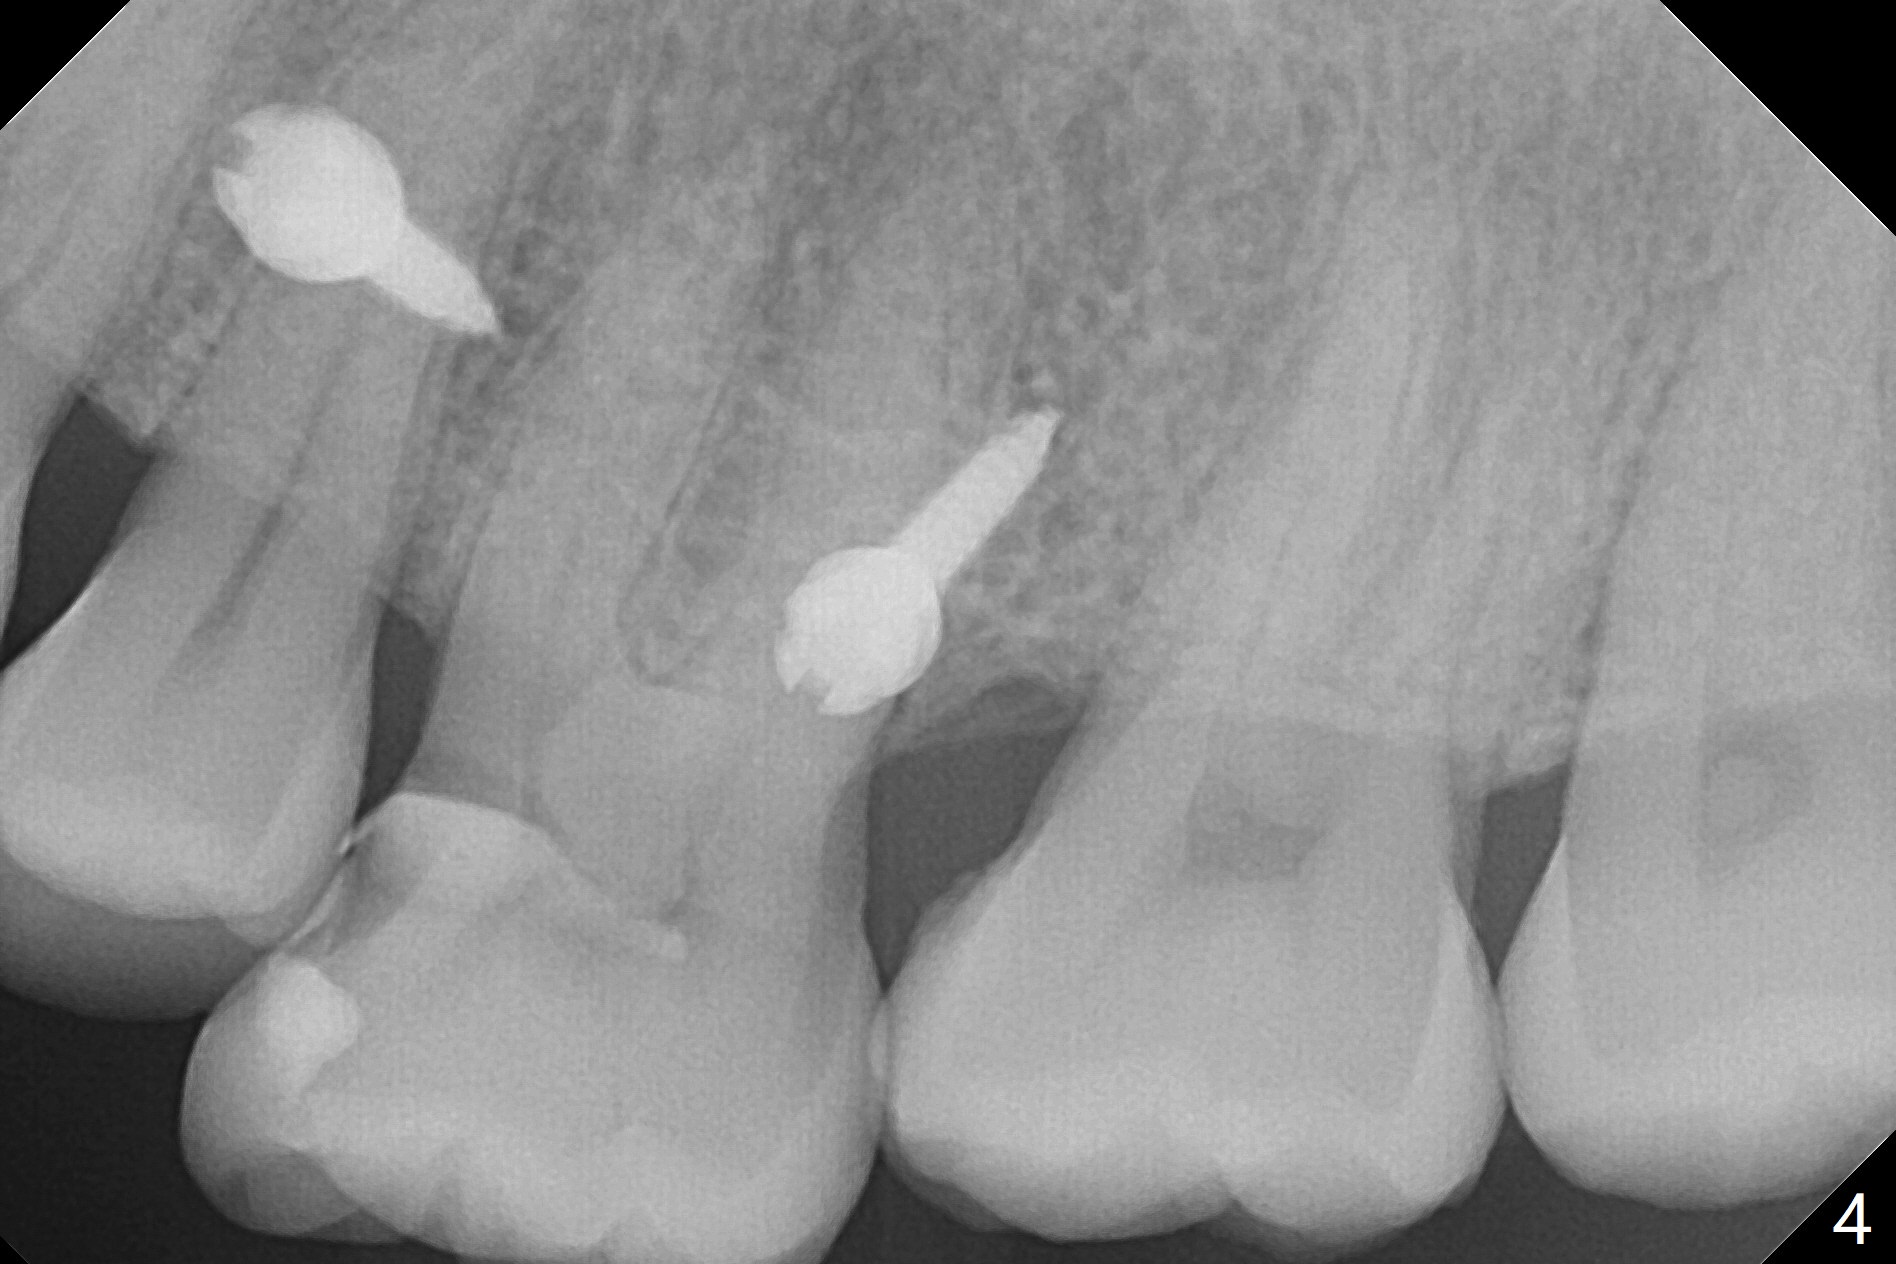

Fourteen days prior to implantation at #19 to replace a flipper (Fig.2), two minimplants are placed to intrude the supraerupted opposing tooth (#14, Fig.1). After use of minimal amount of local anesthetic (to keep proprioceptive in case root surface violation), the miniimplants are inserted ~ half of the length initially (Fig.3,4). The mesiobuccal (MB) one seems to be better positioned than the distopalatal (DP) one. When the implants are completely seated (Fig.5,6), three of PAs are taken, which suggests contact of the MB implant to the MB root of the tooth #14 (Fig.7 arrow). Immediately postop CT confirms approximation of MB and DP implants to the MB and P roots, respectively (Fig.8,9). The trajectory of these implants remain unchanged. Twelve days postop, the patient returns, uncomfortable with the palatal implant. After deep placement to bury the cuff (Fig.6) without local anesthesia (bone having no innervation), the patient feels better.